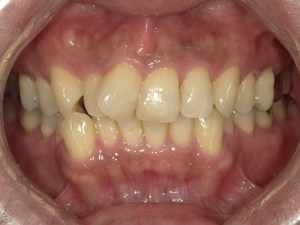

ガタガタとした歯並びや八重歯(叢生)CASE71